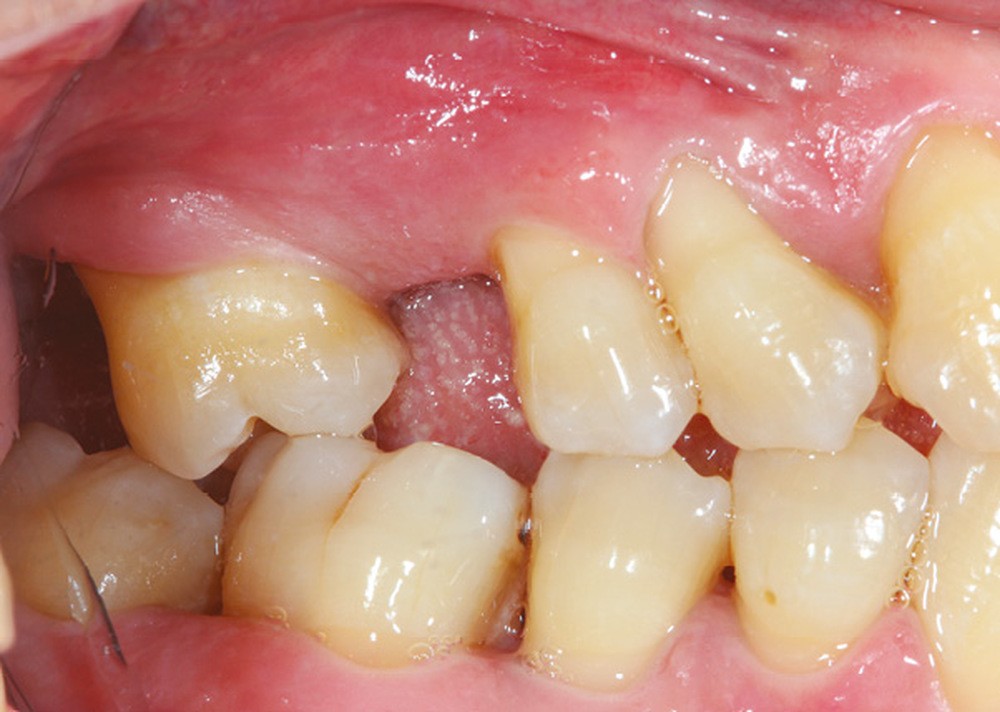

La perte d’une ou plusieurs dents entraîne la perte des points de contact, responsables de la stabilité et de la continuité de l’arcade. Par conséquent, une avulsion a pour première conséquence la migration ou la version d’une ou plusieurs dents distales (fig. 1 et 2). Cela est vrai en antérieur comme en postérieur.

L’âge de survenue de l’extraction semble avoir une importance sur l’apparition des migrations et des versions : si l’édentement intervient après 26 ans, les conséquences sont moins fréquentes [9].

La version des dents distales peut aussi avoir des conséquences parodontales désastreuses : sur un parodonte réduit, une hypermobilité peut se développer, une poche parodontale peut aussi apparaître. Chez un patient parodontal, un « effet domino » est possible, des extractions non compensées diminueront donc le pronostic des dents restantes (fig. 7 à 9).